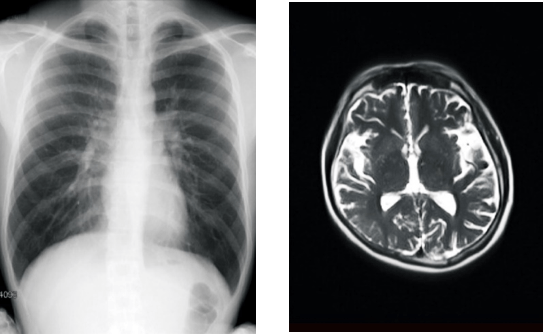

賛育会病院では2021年10月11日より、「カルテコ」で健診情報が閲覧可能になりました。今回新たに、健診・人間ドックで撮影したレントゲン・マンモグラフィ・CT(コンピュータ断層撮影)・MRI(磁気共鳴画像診断)などの検査画像が閲覧できるようになります。21年1月以降の過去のデータまでさかのぼって閲覧することができます。